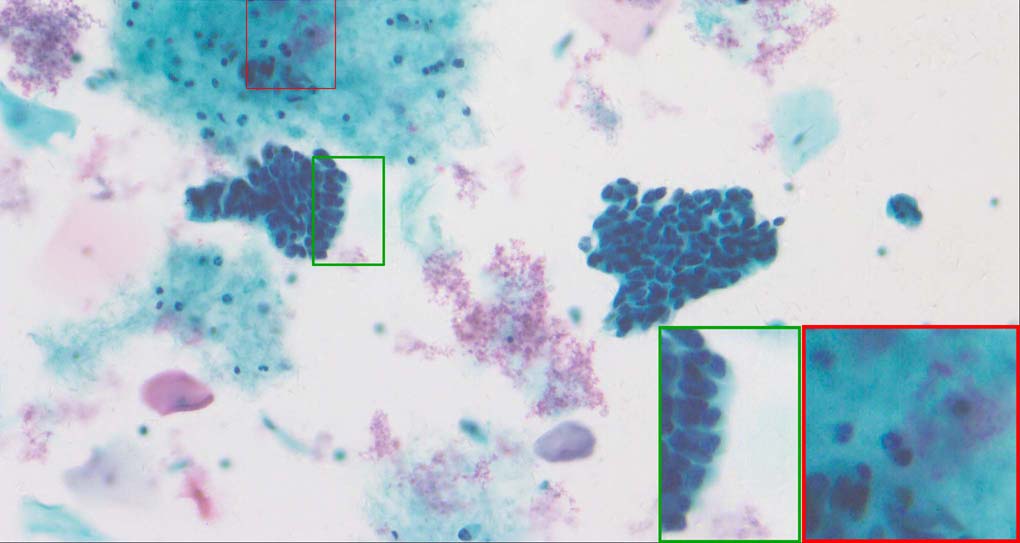

A good image fusion method should contain the following properties. First, it preserves both the details of small size objects and the integrity information of large size objects in the fused image, even in the case of the size of the interested objects varying largely in the image. For example, the cervical cell images from the microscope contain both small size isolated cells and large size agglomerates, which are both useful for cervical cytology [5]. Second, it should be efficient enough to handle large-scale data. For instance, it needs to process thousands of fields of view (FoV) in an acceptable time for the whole slide scanning in digital cytopathology [6], which requires to fuse a series of high resolution images captured at each FoV in a very efficient way. Third, it does not produce obvious artifacts. Despite being studied extensively, to our best knowledge, existing fusion methods may not meet these requirements simultaneously.

In this paper, we propose a simple yet effective image fusion method which can deal with the case where the size of the interested objects varies largely in the image, which is illustrated in Figure 1. It is a spatial domain method and the key idea is the scale-invariant structure saliency generation based on the difference-of-Gaussian (DoG) pyramid [7]. After generating the saliency map of each image, a simple max operation is applied to them to generate the mask images, which are further refined by a single-scale guided filtering [8] to exploit the spatial correlation among adjacent pixels, resulting a scale-invariant estimation of activity maps. Without complicated processing involved, the proposed method is very fast and can be used to fuse the high resolution images in real-time applications. Experimental results demonstrate that comparing to many state-of-the-art methods, the proposed method is much faster while yields competitive or even better results in terms of both visual and quantitative evaluations. Our contributions in this paper are as follows:

To demonstrate the effectiveness and efficiency of the proposed image fusion method , we conduct a set of comparative experiments on three image datasets. The first is composed by 8 pairs of multi-modal medical images and the second one contains 15 pairs of multi-focus gray or color natural images. These two datasets are often used in many related papers and some examples are shown in Figure 3(a) and Figure 3(b). The third one is a new multi-focus cervical cell image dataset collected by ourselves, which consists of 15 groups of color images and each group contains a series of multi-focus cervix cell images with size of or , etc. Some source examples are shown in Figure 3(c). Our source code implemented in C++ along with the new multi-focus cervical cell image dataset is available online.

Figure 9, Figure 10 and Figure 11 show the comparative fused results of the multi-focus cell images shown in Figure 3(c). For clarity, we also present a closeup view in the right-bottom of each sub-picture in Figure 9 and Figure 10. As shown in the close-up views of Figure 9, the fused images based on DSIFT, IM, MWGF and BF methods are extremely blurred in the boundary and fail to keep the details of cell nucleus. Furthermore, the DTCWT and NSCT based methods produce halo artifacts in the fused images, while GFF and CNN based methods fail to preserve the small cell nucleus. LP-SR based method nearly works fine which keeps the most of the details of the small size cells, but the integrity of the clustered large size cells is damaged. Fortunately, in our proposed method, the integrity of the clustered large size cells is preserved and most of the isolated small size cells are maintained from the original images, which demonstrates the best visual quality.